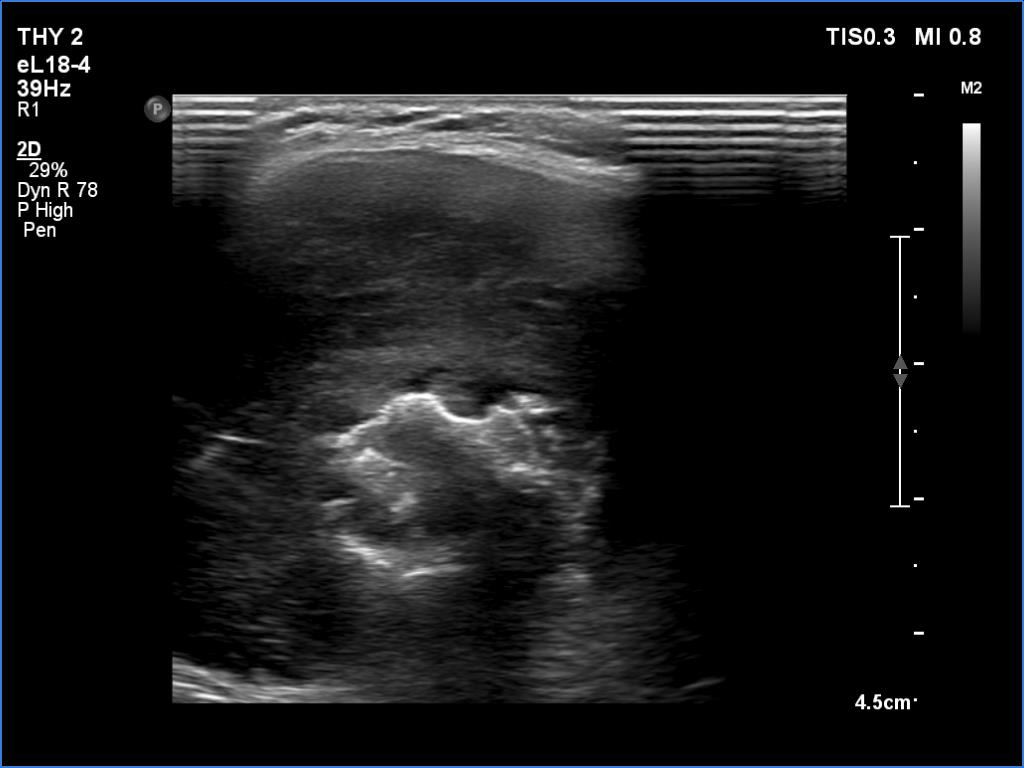

Ultrasonography. There was an irregular, large hypoechoic mass in the right lobe. The nodule has irregular, lobulated margins and was hard on elastography. A much smaller, similar nodule was in the lower-medial part of the left lobe.